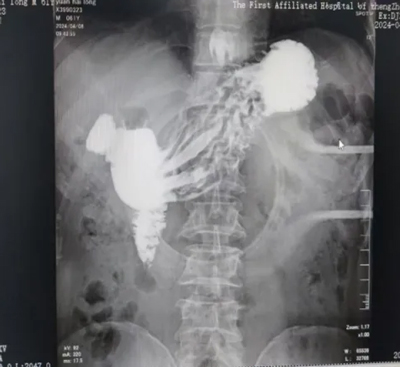

胸部CT

上消化道造影

無痛胃鏡等檢查

結(jié)果顯示為

食管裂孔疝

同時伴有

食管胃粘膜異位

膽汁反流性胃炎

(術(shù)前消化道造影)